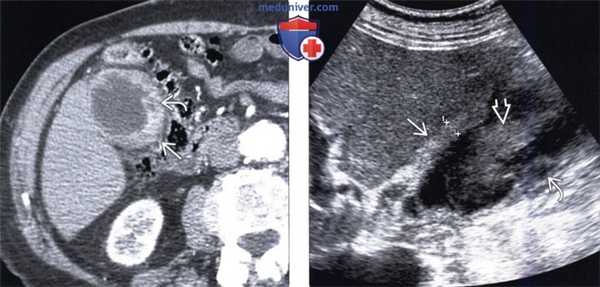

(Слева) На фотографии удаленного желчного пузыря внутри его значительно утолщенной стенки виден интрамуральный абсцессе. Часть печени, прилежащая к желчному пузырю, также была удалена, поскольку во время операции возникло подозрение на рак желчного пузыря. При патоморфологическом исследовании подтвердился ксантогранулематозный холецистит.

(Справа) На аксиальной КТ с контрастным усилением определяется утолщение стенки желчного пузыря, особенно выраженное в области его дна, граница между желчным пузырем и печенью нечеткая. Несмотря на то, что эти изменения подозрительны на рак желчного пузыря, при холецистэктомии был обнаружен ксантогранулематозный холецистит. (Слева) На аксиальной КТ у пациента с жалобами на боль в правом подреберье определяется неравномерное утолщение стенки желчного пузыря, выраженное в значительной степени; видны также несколько включений низкой плотности рядом с желчным пузырем и одно - в его стенке. Гиподенсные интрамуральные узлы при ксантогранулематозном холецистите могут представлять собой как абсцессы, так и ксантогранулемы.

(Справа) На аксиальной КТ без контрастного усиления у пациента с хронической болью в животе визуализируется увеличенный желчный пузырь с толстой стенкой, плохо отграниченный от паренхимы печени. Несмотря на то, что изменения не позволяют исключить рак, при оперативном вмешательстве подтвердился ксантогранулематозный холецистит.

УЗИ (слева) и КТ (справа) желчного пузыря. На УЗИ ярко выраженное утолщение стенки желчного пузыря (указаны белыми стрелками). Множественные камни в просвете желчного пузыря (указано стрелкой). Компьютерная томография с контрастным усилением. На КТ визуализируются утолщение стенки с внутристеночными гиподенсными включениями. На КТ также выявлено, что процесс распространился на печень (указано стрелкой).